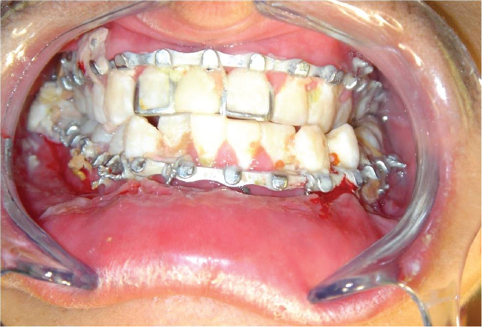

Preoperative examination should include a thorough assessment of occlusion, the dentition, and fracture mobility with bimanual manipulation. The function of the mental nerve should be assessed as well, as any fracture crossing the inferior alveolar canal can result in neurosensory deficits in the lower lip and chin. Although computed tomographic (CT) imaging is standard in facial fractures, most mandibular injuries are adequately assessed with a panoramic x-ray (Panorex) (Figure 14.1) and an anteroposterior (AP) view.

The intermaxillary fixation should be achieved with either elastics or with wire to reestablish what appears to be the pre-injury occlusion (Figure 14.2).